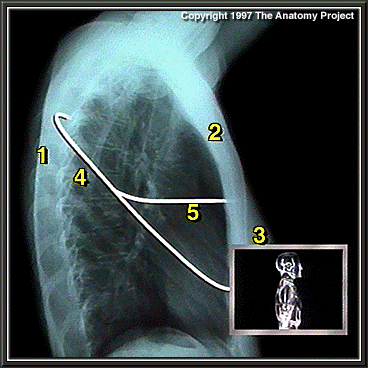

Chest X-ray, lateral view

Rib

Sternum

Breast

Position of oblique fissure

Position of horizontal fissure